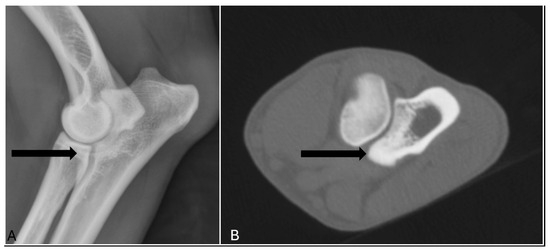

Medical imaging is a vital component in veterinary orthopaedics, offering essential insights into the diagnosis, treatment, and management of musculoskeletal disorders across various species. With the continuous advancement of veterinary medicine, the application of precise imaging techniques, such as radiography (xR), ultrasound (US), computed tomography (CT), and magnetic resonance imaging (MRI), has gained increasing prominence in both clinical practice and research. These modalities enable accurate diagnoses of orthopaedic pathologies, enhancing patient outcomes while also advancing our understanding of animal biomechanics, injury mechanisms, and recovery dynamics.

This Special Issue, “Medical Imaging in Veterinary Musculoskeletal Diagnosis”, aims to deepen and update knowledge on the importance of orthopaedic imaging diagnosis in veterinary medicine. Therefore, the inclusion of clinical or experimental research work is encouraged. The research can be based on any type of medical imaging modality (e.g., xR, US, CT, MRI), in different veterinary species: companion animals, species of livestock interest, sport animals, or exotic or wild animals. Through a collection of research articles, reviews, and expert opinions, this Special Issue will contribute as an important resource for veterinarians and researchers on orthopaedic veterinary imaging diagnosis.